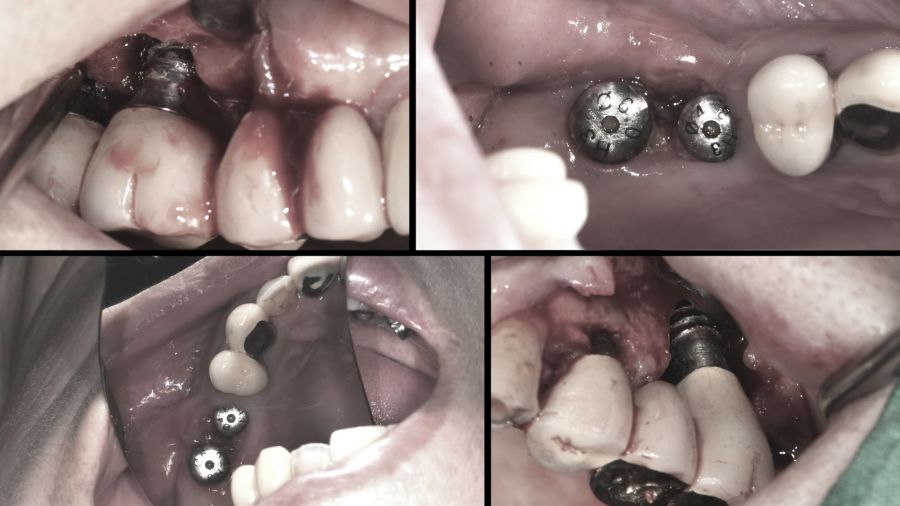

착잡한 얼굴로 병원을 찾은 70대 남성. 남성은 10여 년 전 상악에 심은 임플란트 대부분을 제거하고 남은 한 개로 임플란트 틀니를 사용하고 있었다. 하지만 그마저도 염증이 발생해 더 이상 사용이 어려워졌다. 남성은 임플란트 재식립을 원하지만 염증으로 치조골이 심각하게 녹아 재식립이 어려운 상황. 결국 남은 선택지는 틀니밖에 없었다.

임플란트 식립의 가장 중요한 조건은 충분한 양의 치조골이다. 그런데 임플란트 주위염은 치주염보다 훨씬 더 진행 속도가 빠르며 치주조직과 뼈를 파괴적으로 손상시키기 때문에 조기에 치료하지 않으면 임플란트가 헐거워져 빠지게 되고, 그 이후 재식립도 할 수 없다.

3개월에 한 번 씩 정기검진을 받는다는 70대 남성. 하지만 불과 몇 년 전만 해도 치과를 자주 찾지 않았다는데… 그 결과는 끔찍했다. 식립한 임플란트 주위에 염증으로 잇몸이 녹아내린 것. 잇몸 일부를 잃고 나서야 관리의 소중함을 깨달았다는 남성. 실제로 많은 사람들이 임플란트를 식립하면 모두 끝이라고 생각한다.